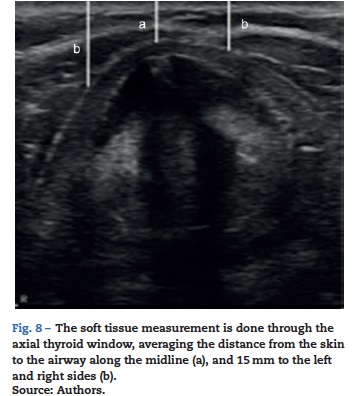

There is growing academic interest in the use of ultrasound to identify the difficult airway predictors; though still under discussion, there are increasing numbers of papers on the topic, particularly to measure the pre-tracheal fat in obese patients. A transverse window at the level of the vocal cords is used for proper measurement, and then the anteroposterior diameter is measured at the midline from the skin of the trachea to 15 mm of the right and left sides. If the sum of these three measurements exceeds 28 mm in a patient with a neck circumference larger than 50 cm and a BMI>35kg/m2, is predictive of a difficult laryngoscopy - Cormark visualization 3 or 4, in 70% of the cases (Fig. 8). According to Ezri et al.,20 all patients with difficult laryngoscopy were positively correlated with increased pre tracheal fat at the level of the vocal cords.20,21